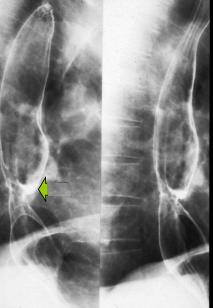

Oesophagite caustique 1/3 moyen de

oesophage avec aspect lesionaire c'est imsage

stenose cicatricielle a bord lisse de perdre

elasticite ( fleche blanche ) |

|

Une autre cas de

oesophagite caustique . La lesion etendue le long

2/3 superiere de oesophage . Image radiologique du

transit oesophagien en OAD |